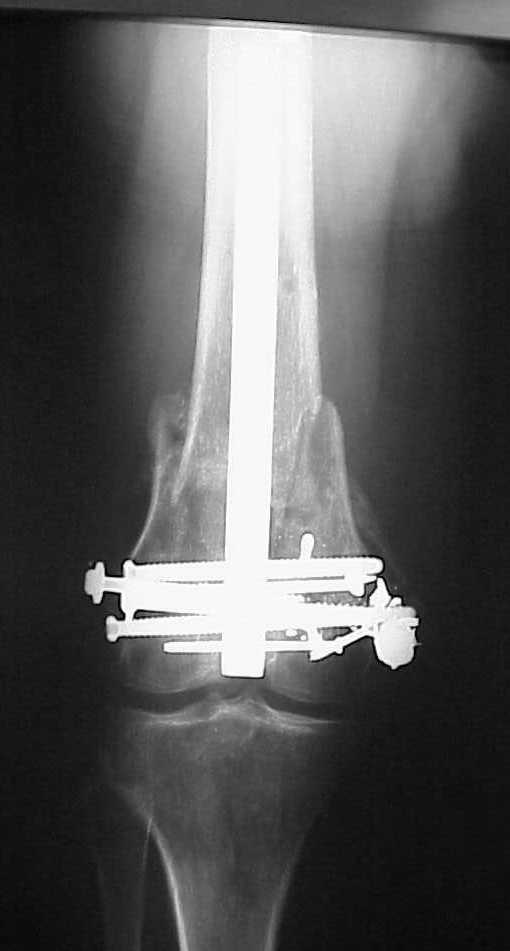

Да, примерно так и сделали. Надо было, пожалуй, кончик гвоздя еще спилить, чтобы отверстие было еще дистальнее. Англоязычные коллеги еще

советовали винты в передне-заднем направлении вводить, но что-то не увидел, где там подходящее место.

Since it was done closed the shaft will heal or at worst need an exchange IMN.

Nice job.

Мы пошли на операцию с планом попытаться сделать закрытый интрамедулярный, а не получится - сделать аппаратом. Посчитали, что получилось, хотя на еженедельной конференции ожидаются некоторые проблемы с объяснениями ;-)

Насчет стабильности для ранней нагрузки, конечно, сомнительно, но при таком повреждении ранняя нагрузка противопоказана в любом случае. Для ранних движений Должно хватить. Снимки в следующем сообщении.

IM nails are very forgiving but there are limits. I've seen cases with this postop appearance heal nicely.

The advantages of retrograde nail in this situation are: easier insertion, easier reduction and better distal fixation.